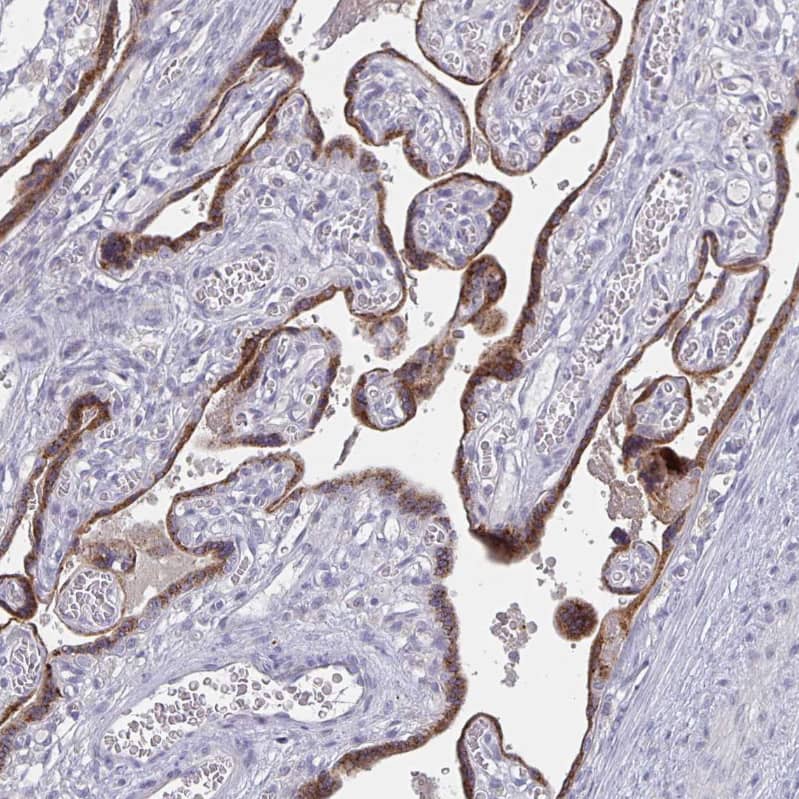

Staining of human placenta shows moderate granular cytoplasmic positivity in trophoblastic cells.